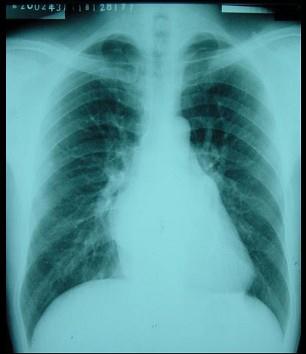

问题 男性,30岁。活动时心慌、气促两年,加重一年,一年前出现“脑栓塞”,心律98次/分,心律绝对不齐,心尖可闻及中重度舒张期隆隆样杂音,胸骨左缘3、4肋间可闻及Ⅱ~Ⅲ/6级收缩期杂音。 该病人最可能的诊断是 ( )

选项 A、二尖瓣关闭不全 B、法洛四联症 C、主动脉瓣狭窄 D、二尖瓣狭窄合并三尖瓣关闭不全 E、室间隔缺损

答案 D